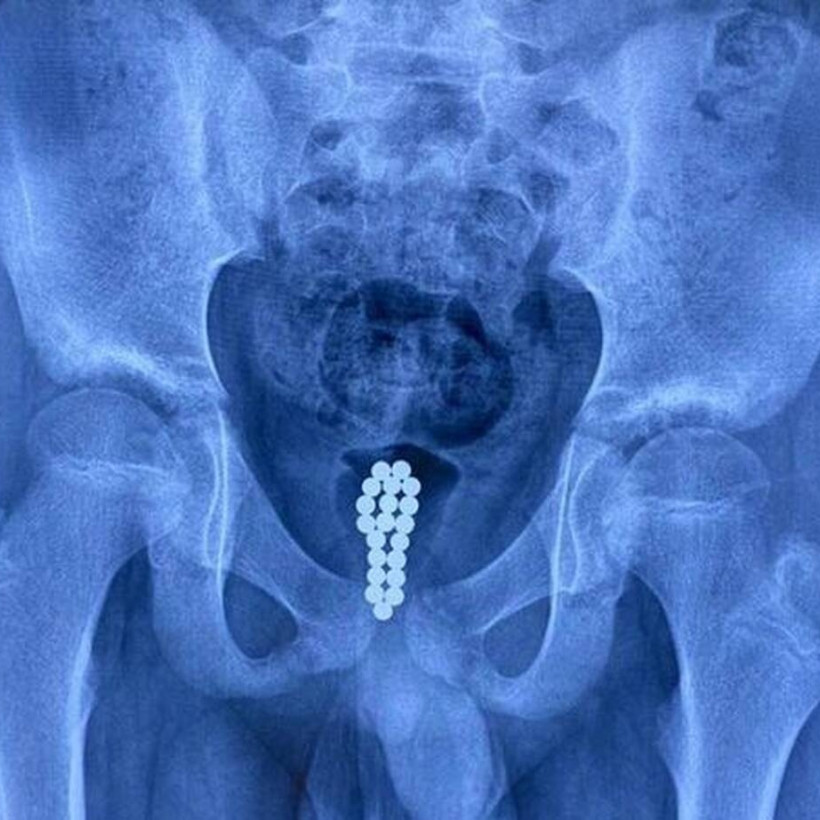

Το παιδί ένιωθε ενοχλήσεις στο μόριό του για αρκετό καιρό, ωστόσο δεν είχε πει το παραμικρό στους γονείς του. Κάποια στιγμή το παιδί, έφτασε στο σημείο να μην μπορεί να ουρήσει και μοιραία κατέληξε στα επείγοντα περιστατικά.

Εκεί οι γιατροί, μόλις είδαν την ακτινογραφία του παιδιού το έβαλαν αμέσως στο χειρουργείο ενώ δεν πίστευαν ούτε οι ίδιοι σε αυτό που αντίκριζαν.

Τι είχε το παιδί; Δείτε στην παρακάτω gallery και πραγματικά θα μείνετε με το στόμα ανοιχτό: